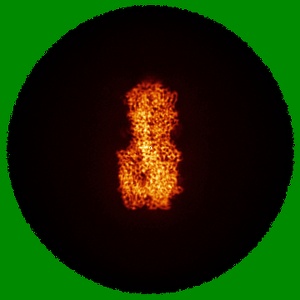

Influenza A Virus Group 2 Hemagglutinin (H7, Strain SH13) in Complex with the Potent Small-Molecule Entry Inhibitor SA-67

Mechanistic insights into the small-molecule inhibition of influenza A virus entry.

Xu Y, Anirudhan V , Gaisina IN , Du H, Alqarni S , Moore TW , Caffrey M, Manicassamy B , Zhou T, Rong L , Xu K

(2025) PNAS , 122 , e2503899122 - e2503899122